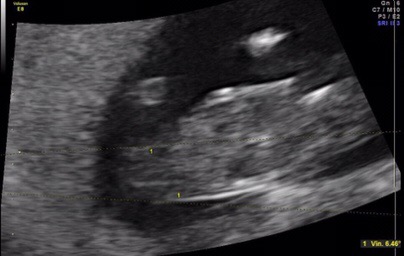

13 weeks 2 days NUB and skull guesses please

First of all, I know the shots are really bad. I have a really uncoperative baby combined with an anterior placenta which makes images less clear.

Anyway, the baby Measured 13 weeks 2 days and I wonder IF anyone is willing to try and guess either by nub or skull.

My doctor who performed the Scan gave a 95% girl guess despite unclear shot. He has 40 years experience in pregnancy ultrasounds and he correctly confirmed My sons gender at 11 week 5 Days a few years back.

I don't dare to trust IT.... Really hope for a girl. But From looking at it, the nub looks elevated to me. As in pointing upwards and therefor indicating boy.

At My 11 week 2 day NT scan he said IT was difficult but he had a girl lean already back then 2 weeks ago.

The nub was flat by then, but got mostly boy votes online due to "stacking".

Here I am asking Again, what do you guys think? Nub Theory? Skull theory?